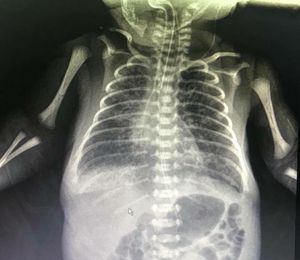

A 27weeks gestation male premie was admitted in NICU 6 days ago, his birthweight was 990g and apgar score at birth were 4 and 7 at 1 and 5 min, severe RDS was onset after 1 hour of his life and the endotracheal intubation was performed followed by the PS administration, he was put on HFOV , a GI tube was inserted and the enteral feeding was started with EBM at the second day of his life, well tolerated. This morning I rounded the ward and found he developed mild RDS manifested by intercostal retractions and the O2 saturation was suboptimal, around 87~91%, so I had to increased MAP from 9cmH2O to 11cmH2O, then his saturation got better and intercostal retractions improved, by auscultation, there are lots of rales in his bilateral lung fields and the sounds of aeration were not equal, the sound of his right side was much weaker than the left, the CXR was attached here, how to interpret it and what shall I do next?